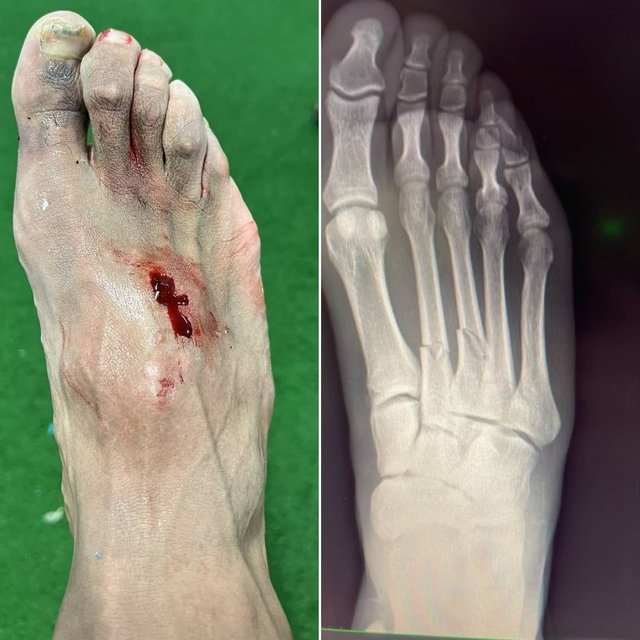

В середине второго тайма матча против Кадиса Карло Анчелотти выпустил бельгийца, который должен был помочь дожать аутсайдера. А хавбек едва не подставил команду. Азар грубо сфолил против Карлоса Акапо. Повезло, что арбитр ограничился только желтой.

А вот для игрока Кадиса игра завершилась досрочно. Оказалось, что Азар сломал Акапо вторую и третью плюсневые кости.